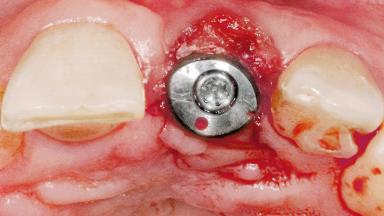

Late Flapless Placement of an Implant in a Maxillary Left Central Incisor Site

Type of Implants One-Piece

Attachment One-Piece

Soft Tissue Grafting Simultaneous

Abutment Type Standard